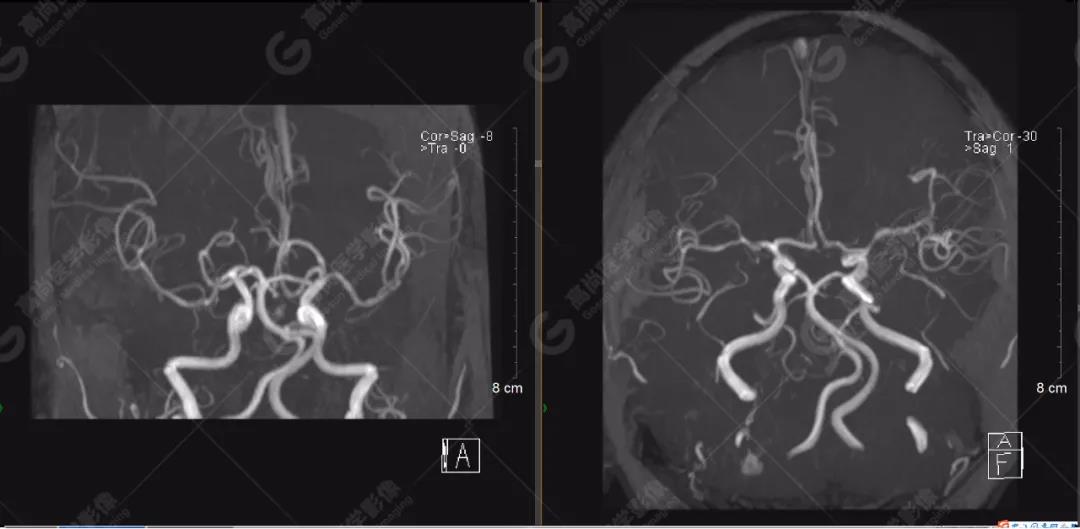

顱腦MRA及ciss序列示腦基底動(dòng)脈環(huán)完整,雙側(cè)頸內(nèi)動(dòng)脈末段、大腦前動(dòng)脈、大腦中動(dòng)脈、大腦后動(dòng)脈及其主要分支顯影良好,管徑及走行正常,無明顯局灶性增粗或變細(xì)。雙側(cè)椎動(dòng)脈末段沿延髓左側(cè)向上走行,左側(cè)面聽神經(jīng)輕度受壓移位,左側(cè)面聽神經(jīng)周圍見細(xì)小血管包繞。右側(cè)面聽神經(jīng)及雙側(cè)三叉神經(jīng)周圍未見異常血管影。

1.雙側(cè)椎動(dòng)脈末段沿延髓左側(cè)向上走行,左側(cè)面聽神經(jīng)輕度受壓移位,左側(cè)面聽神經(jīng)周圍見細(xì)小血管包繞,可符合面聽神經(jīng)壓迫綜合征。